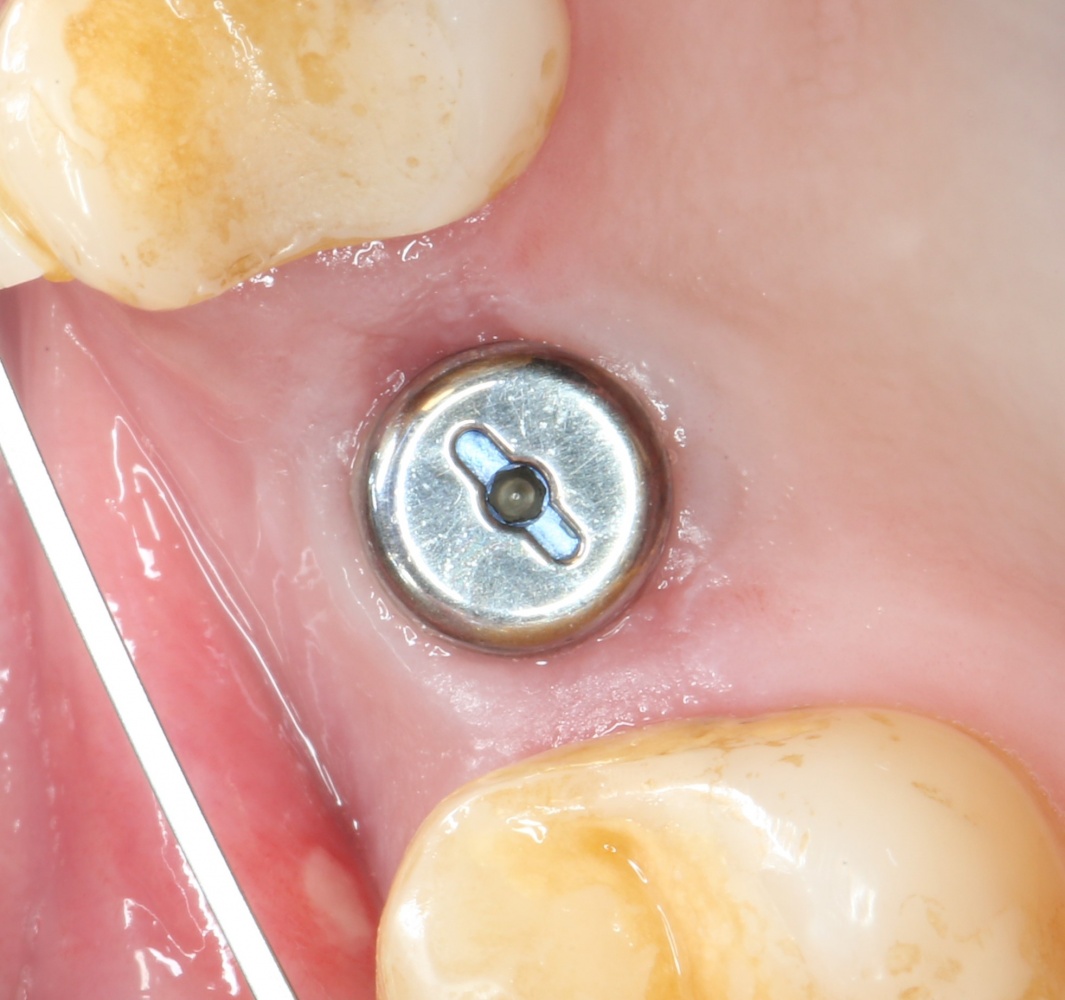

Устанавливаем формирователи десневой манжеты. Сегодня я называю эту процедуру не менее важной, чем любой другой этап имплантологического лечения:

И швы. Просто швы. Никаких дополнительных процедур.

Если честно, то сейчас бы я использовал другой шовный материал и другой тип швов. Одно неизменно, — и я об этом много раз говорил, — самая широкая часть формирователя десны должна находиться на уровне десны. Так, чтобы эффективно отрабатывать т. н. «биологическую ширину».

Через неделю я снял швы, а мой коллега Андрей Карнеев (дело было еще в НИЦ) приступил к изготовлению протезов. На это ушло полторы недели: